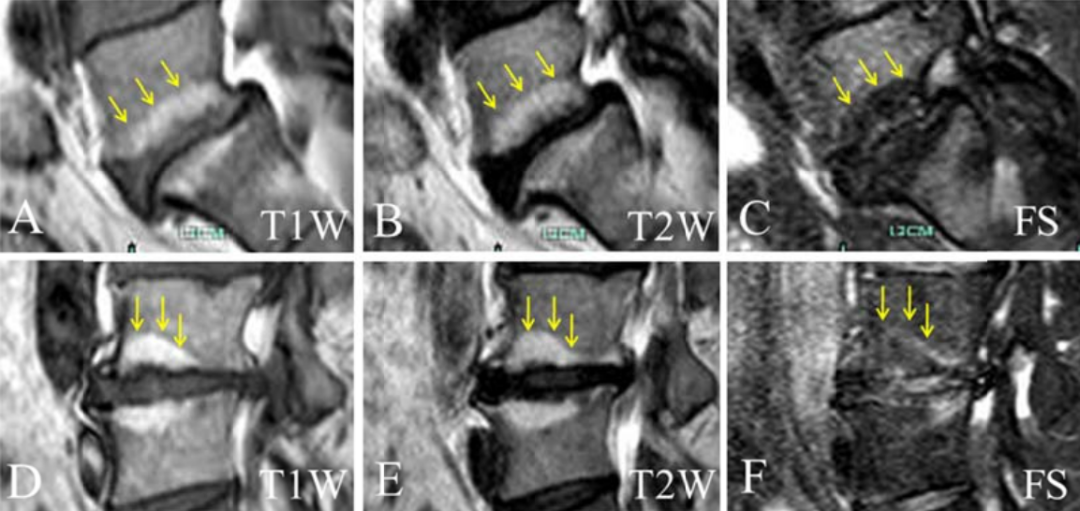

Modic影像表现:

Ⅰ型:组织学表现为终板及终板下区域有丰富的肉芽组织长入, 纤维血管组织代替了增厚的骨小梁间的正常骨髓,从而延长了椎体 T1、T2 驰豫时间,T1WI 上终板及邻近骨质表现为低信号,T2WI 上表现为高信号,抑脂序列呈高信号,表明骨髓水肿。

Ⅱ型:组织学表现为骨髓脂肪变性或骨髓缺血坏死,导致 T1 及 T2 时间缩短,在 T1WI 上呈高信号,T2WI 表现为稍高信号,抑脂序列呈低信号;

Modic Ⅰ型:

L4-5椎间盘上下缘见条带状异常信号,T1WI低信号,T2WI高信号,STIR序列高信号。

L5-S1椎间盘上下缘见条带状异常信号,T1WI低信号,T2WI高信号,STIR序列高信号。